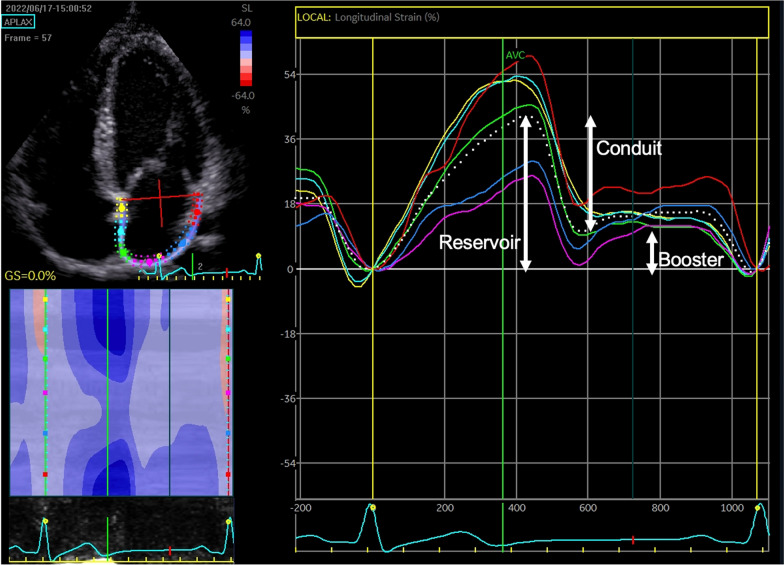

Methods: Utilising a cross-sectional design, male (n = 81) and female (n = 15) RT individuals were grouped based on IPED user status: current (n = 57), past (n = 19) and non-users (n = 20). Participants completed IPED questionnaires, anthropometrical measurements, electrocardiography, and transthoracic echocardiography with strain imaging. Structural cardiac data was allometrically scaled to body surface area (BSA) according to laws of geometric similarity.

Results: Body mass and BSA were greater in current users than past and non-users of IPEDs (p < 0.01). Absolute left atrial (LA) volume (60 ± 17 vs 46 ± 12, p = 0.001) and right atrial (RA) area (19 ± 4 vs 15 ± 3, p < 0.001) were greater in current users than non-users but this difference was lost following scaling (p > 0.05). Left atrial reservoir (p = 0.008, p < 0.001) and conduit (p < 0.001, p < 0.001) strain were lower in current users than past and non-users (conduit: current = 22 ± 6, past = 29 ± 9 and non-users = 31 ± 7 and reservoir: current = 33 ± 8, past = 39 ± 8, non-users = 42 ± 8). Right atrial reservoir (p = 0.015) and conduit (p = 0.007) strain were lower in current than non-users (conduit: current = 25 ± 8, non-users = 33 ± 10 and reservoir: current = 36 ± 10, non-users = 44 ± 13). Current users showed reduced LV diastolic function (A wave: p = 0.022, p = 0.049 and E/A ratio: p = 0.039, p < 0.001) and higher LA stiffness (p = 0.001, p < 0.001) than past and non-users (A wave: current = 0.54 ± 0.1, past = 0.46 ± 0.1, non-users = 0.47 ± 0.09 and E/A ratio: current = 1.5 ± 0.5, past = 1.8 ± 0.4, non-users = 1.9 ± 0.4, LA stiffness: current = 0.21 ± 0.7, past = 0.15 ± 0.04, non-users = 0.15 ± 0.07).

Conclusion: Resistance trained individuals using IPEDs have bi-atrial enlargement that normalises with allometric scaling, suggesting that increased size is, in part, associated with increased body size. The lower LA and RA reservoir and conduit strain and greater absolute bi-atrial structural parameters in current than non-users of IPEDs suggests pathological adaptation with IPED use, although the similarity in these parameters between past and non-users suggests reversibility of pathological changes with withdrawal.